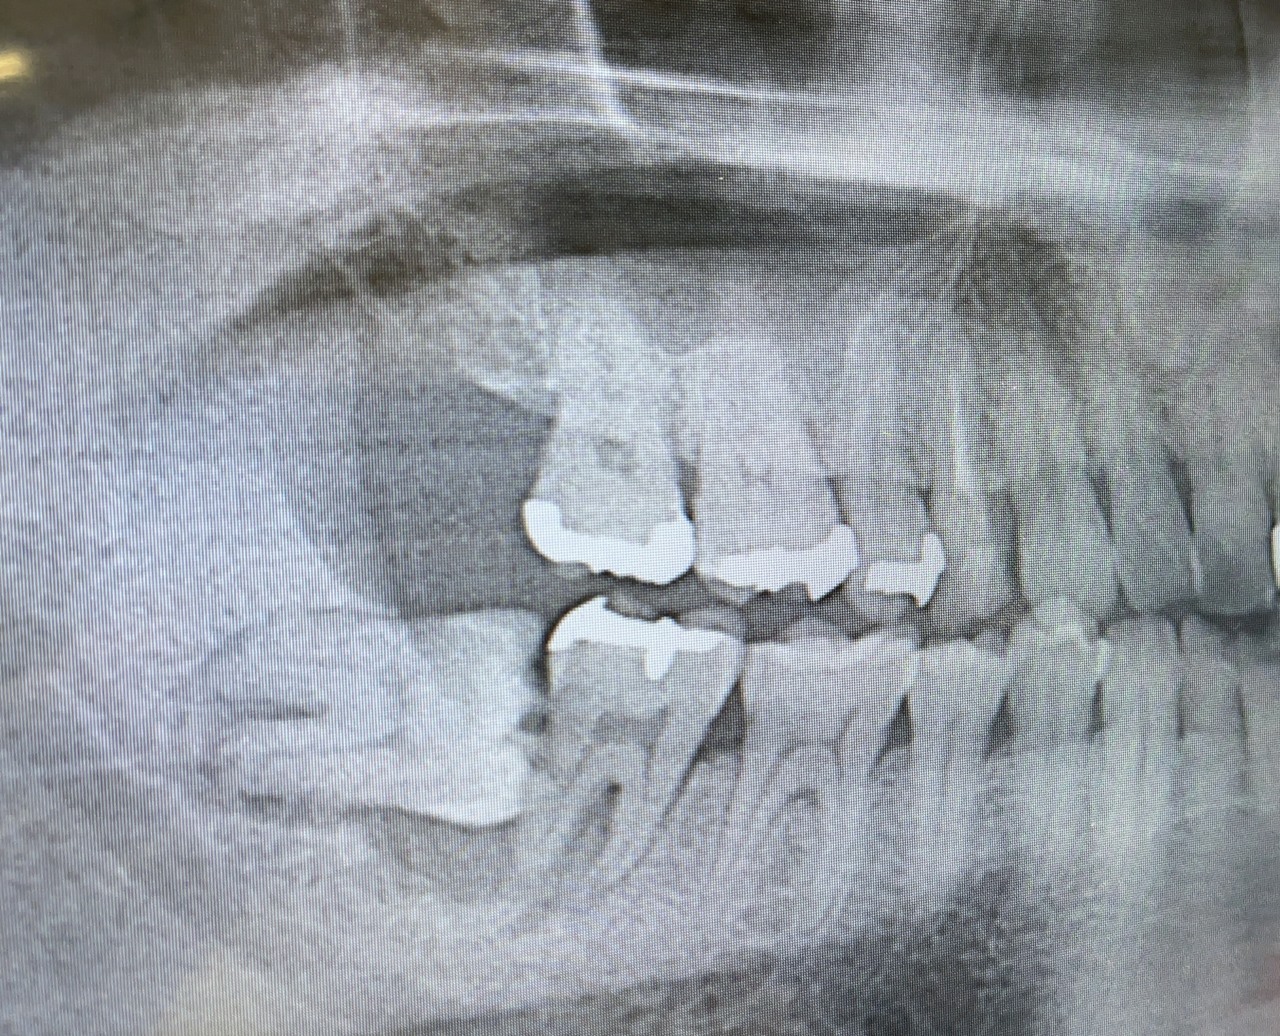

今日は歯医者に行ってから、久しぶりに軽く走ってきた。先日書いた通り色んなところの調子が悪いが、歯科に行って改めて気になっている部分。それはこの歯だ。

まず上の画像。確か2021年の夏に、中小企業診断士1次試験が佳境に入る前に抜いてしまおう、ということで抜いた親知らず。こいつが悪さをした結果が下の画像だ。赤い部分、よく見ると穴がほげている。ここ、実質骨がないので歯が浮いている。こいつに力が加わると痛いし、噛めない。さらにここは空洞になっているようで、ほっておくと歯周病になっていくようだ。それ以外にも歯周病が進みつつあるということがわかったので、色々手を施す必要がありそうだ。しかしこの土台がいない奥歯、インプラントにせにゃならんのだろうなあ。歯医者さんでは、とりあえず抜くと言われているが、もうしばし温存して今後を考えることにする。